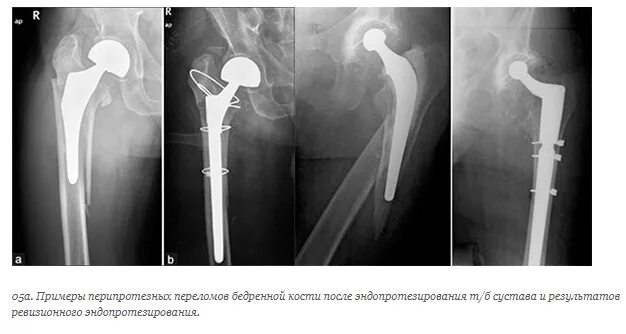

Можно ли после эндопротезирования тазобедренного сустава